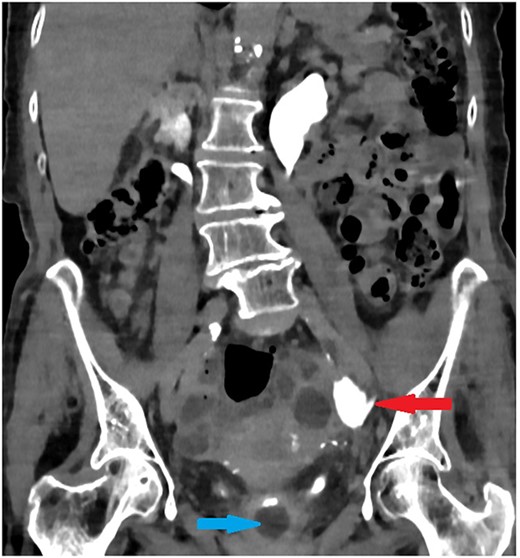

The old catheter was removed, and a replacement was inserted correctly into the bladder. The patient was managed conservatively with antibiotics. A further contrast CT was performed and showed mild extravasation of the contrast at the same level of the former catheter’s inflated balloon (Fig. 2). The patient improved clinically with conservative management, and her blood investigations remained stable. Follow-up contrast CT after 2 months was normal and showed no extravasation and no stricture (Fig. 3).

Coronal section of abdomen and pelvis contrast CT 24 h from the initial CT: The new urethral catheter balloon in the bladder (blue arrow). Contrast extravasates the left ureter at the site of the old catheter balloon (red arrow).